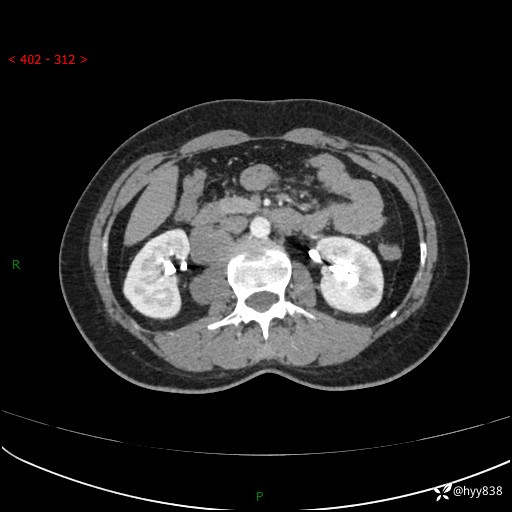

现在都流行跨界,病变也不例外,从腹膜后长到胸腔了---结果公布~

主诉:体检发现右侧腹膜后肿物1天

简要病史:患者于1天前因体检发现右旁肾占位,无肉眼血尿,无畏寒发热,无咳嗽咳痰,无腰腹部疼痛不适,无尿频尿急症状,起病来,患者未行特殊治疗,为求进一步诊治,门诊以"右侧腹膜后肿物"收治入院。 发病来患者精神、饮食、睡眠良好,小便如上,大便正常,体重无明显变化。

临床诊断:腹膜后肿物

上腹部CT增强(动脉期+实质期)(外院平扫)